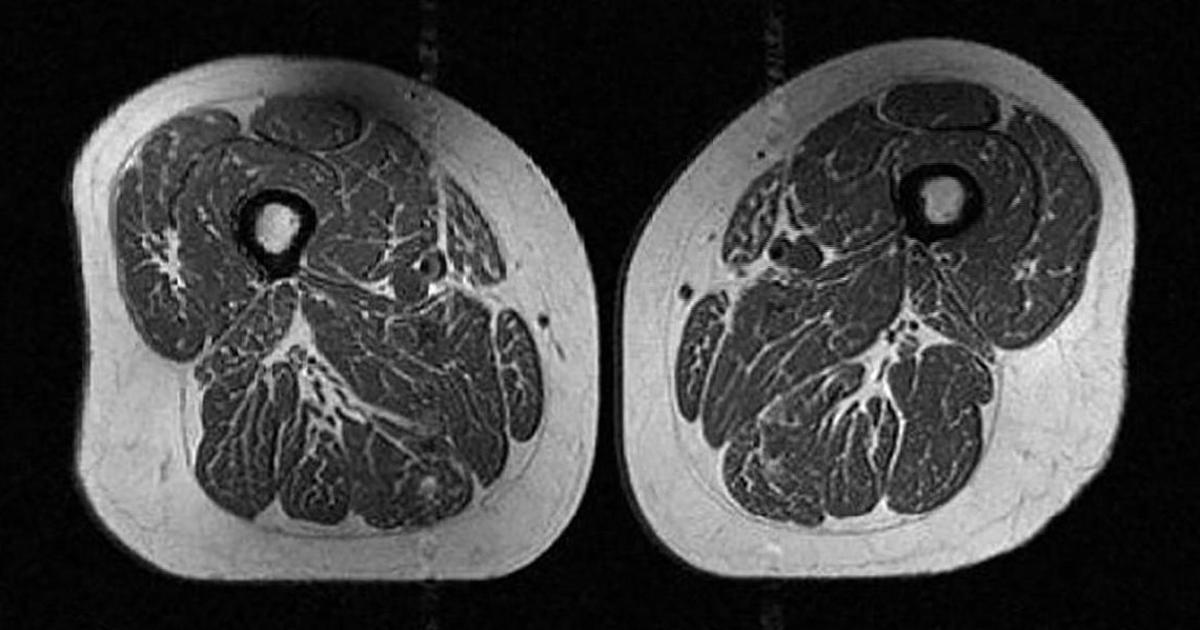

На первый взгляд это изображение можно принять за срез мраморной говядины с жировой прослойкой. Но на самом деле это МРТ-скан бедра 62-летней женщины, чей годовой рацион на 87% состоял из ультрапереработанных продуктов.

По словам доктора Зехры Аккаи, исследовательницы и консультантки группы клинической МРТ-диагностики опорно-двигательного аппарата в Калифорнийском университете в Сан-Франциско, диета этой участницы в основном состояла из сухих завтраков, шоколадных конфет или батончиков, а также газированных сладких напитков. Подобные продукты связывают с набором веса, ожирением и развитием хронических заболеваний, включая рак, сердечно-сосудистые патологии, диабет второго типа и депрессию. Такая еда может даже сокращать жизнь.

Зехра Аккая утверждает, что скрытые жировые прослойки внутри мышечных волокон и между ними могут сигнализировать о серьезных проблемах со здоровьем.